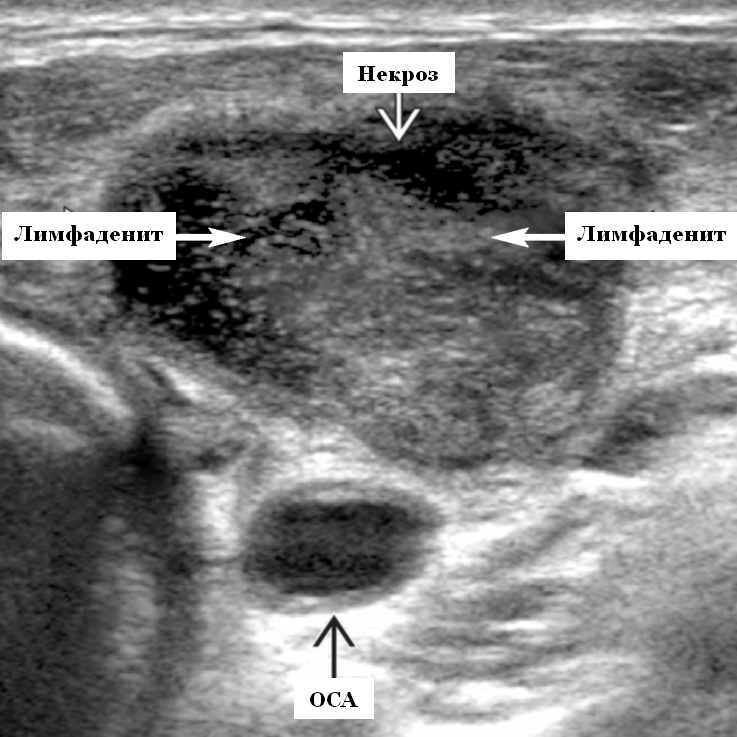

Мезентериальные лимфатические узлы: УЗИ и диагностика

Раздел: Лаборатория идей